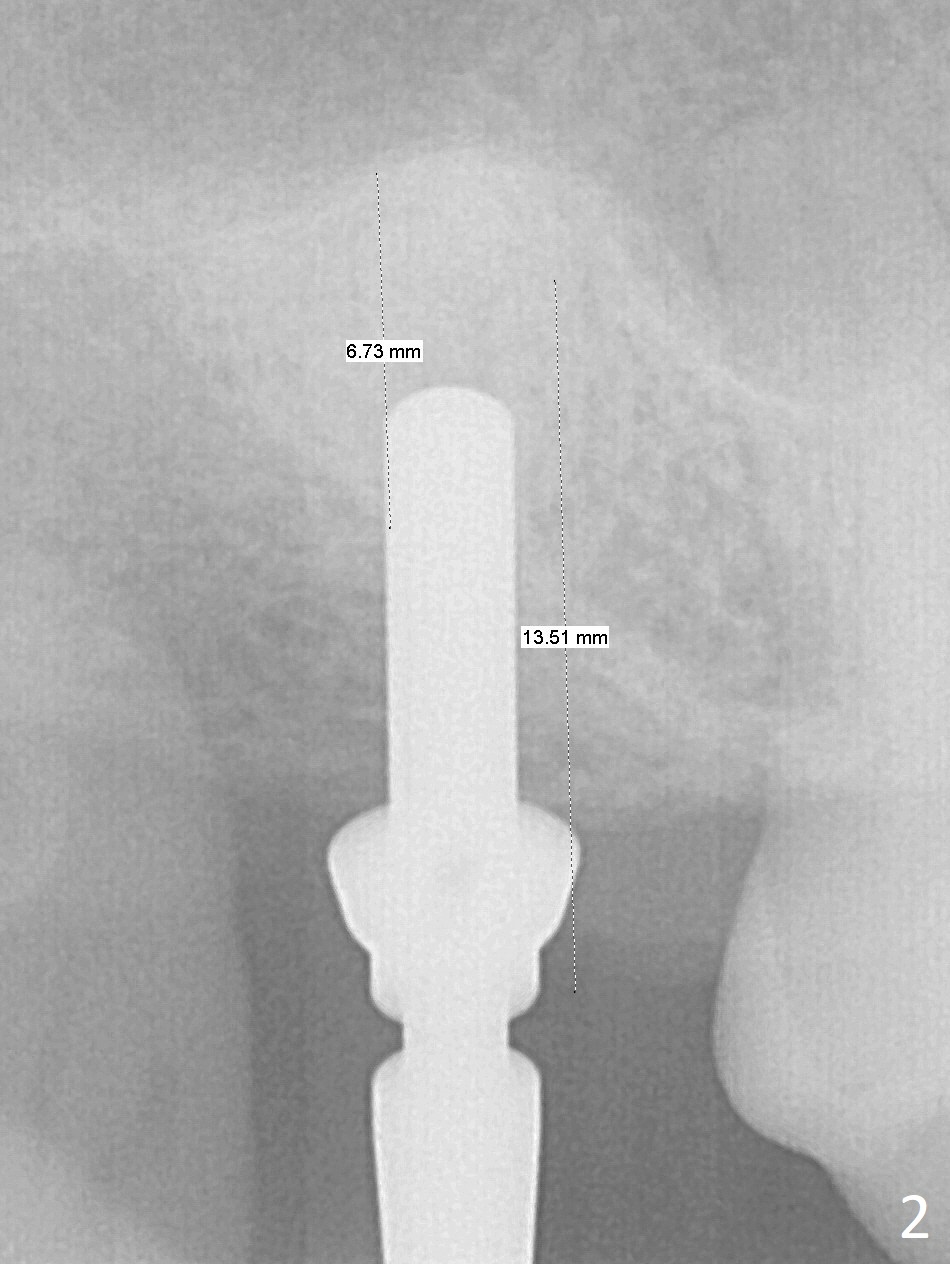

After extraction of the 3rd molar with mesial periodontal defect, osteotomy for 2nd molar implant is initiated in the mesial slope of the 3rd molar socket (Fig.1 red dashed line). When osteotomy is finished with IS drills and sinus lift with Magic Sinus Lifter (S-reamer with 11 mm stopper being short), a 4x10 mm dummy implant is placed with ~ 4 implant thread exposure (Fig.3). Following use of Lindamann bur to move osteotomy mesial and larger drill, a 4.5x10 mm implant is placed with 5-7 implant threads exposed distally (Fig.4,7 (~ 50 Ncm)). The bucco(B)-palatal(P) extent of the implant thread exposure is larger (Fig.5) than that associated with the 4 mm dummy implant (data not shown). The exposed implant surface is covered with Vera Graft (Fig.7*), Collagen plug and an immediate provisional after adjustment of abutment height (Fig.6,7). The bone density distal to the implant is low 3 months postop (Fig.8,9 CBCT) and 3.5 months postop (Fig.10,11). The permanent crown is cemented nearly 4 months postop. The distal cortical bone contacts the implant (Fig.12 ^), while the mesial bone increases in density (*) 2 years postop.